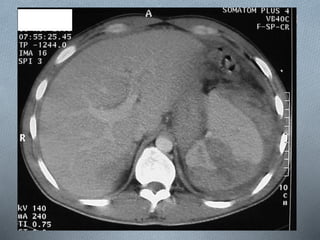

a - Hematomas: únicos o múltiple con un centro de

alta

densidad rodeado de otro de baja densidad. Diferentes

trabajos han comunicado una frecuencia de hasta un

a - Hematomas:únicos o múltiple con un centro de alta densidad rodeado de otro de baja densidad. Diferentes trabajos han comunicado una frecuencia de hasta un 12% de hematomas subcapsulares con una capacidad de resolución hasta de ocho semanas. Los intraparenquimatosos pueden tardar hasta 6 meses en curarse. b - Laceraciones: son lesiones lineales o en ramas. c - Fragmentación: se produce por avulsión no realza con el contraste. d - Hemorragias periportales. Hipodensas. Suelen aparecer hasta en el 65% de los pacientes.